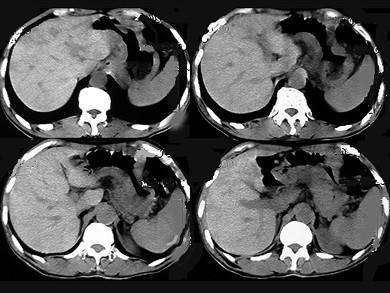

问题 患者50岁,男性,中上腹饱胀、疼痛半年,消瘦,CT扫描如图,应诊断为 ( )

选项 A、胃窦溃疡梗阻 B、胃平滑肌瘤 C、胃腺瘤 D、胃癌 E、淋巴瘤

答案 D